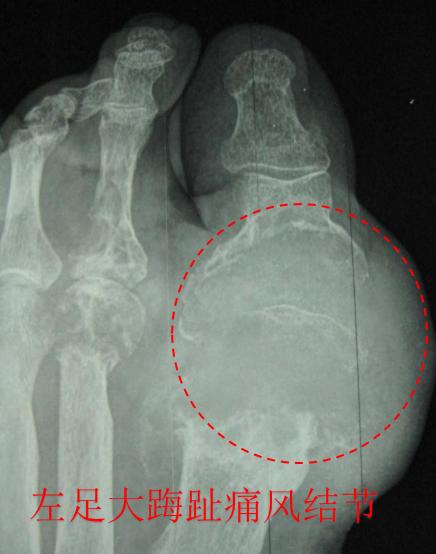

危险的警戒信号—痛风结节

如何尽可能延缓痛风病情的进展、快速缓解疼痛、减少或避免对人体的损害是目前医学界研究的重点。研究发现,如果人体血清尿酸值长时间>535μmol/L,至少50%的病人最终会罹患痛风结节,而且血清尿酸的浓度越高,持续时间越长,产生痛风结节的可能性越大。痛风结节的出现,表明痛风已经开始对人体造成不可逆转的损害了。

痛风结节是痛风的特征性病变,是由于人体内血尿酸浓度长时间处于一个较高的水平,尿酸盐结晶沉淀在内脏、关节等部位,久而久之形成了一种"结节样异物",其大小不一,小如沙粒,大如鸽蛋。除了中枢神经系统,尿酸盐结晶能够在人体所有器官和组织内沉积,其中最常见的是肾脏、胆囊或耳廓软骨、手指、足趾等关节。

一旦我们体内出现痛风结节,又放任不管,痛风结节内部逐渐发生纤维化和钙化。到了这一阶段,想通过降尿酸药物溶解结节,是不可能的。根据结节形成部位的不同,会有不一样的危害和痛苦,常见的3个部位包括:

- 关节:首先尿酸结晶的刺激,会诱发机体产生一系列炎症反应,导致关节附近的骨质、骨髓被破坏,造成关节畸形、骨质疏松,最终导致关节活动障碍;其次痛风结节逐渐变大,表面皮肤紧绷、变薄,一旦受到摩擦、受压、冷热刺激或外伤时,皮肤很容易破溃,会流出白色豆腐渣样的尿酸结晶,合并感染的时候往往导致伤口不能愈合,严重者可能导致截肢。